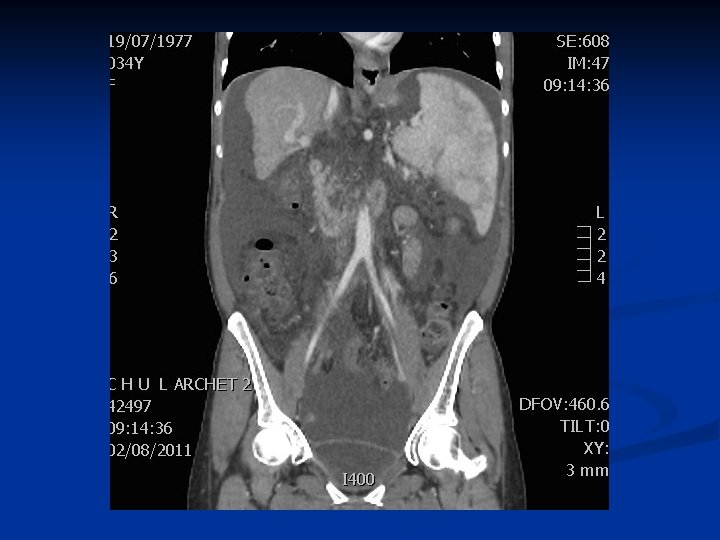

Ascite + Cirrhose

Diagnostic étiologique n Biologie NFS, électrophorèse des protéines sériques, TP, enzymes hépatiques n Bilan rénal (Cl créatinine, iono sg et U) n Bilan cardiaque (insuffisance cardiaque) n n Imagerie Echographie abdominale (foie, circulation collatérale portosytémique, structures digestives et gynécologiques) n TDM ou IRM n